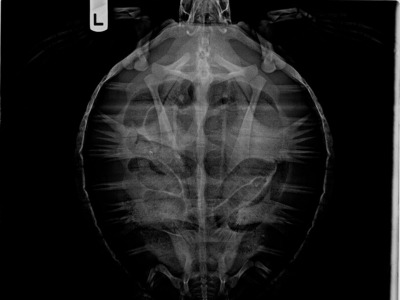

9.3 lb non-FP juvenile green.

Skin lesions on soft skin, severe plastron abrasions, minor carapace abrasions.

In-house PCV = 30%, TP = 4.2 g/dl, glucose = 113, started on Ceftazidime, Vit B Complex, Meloxicam, Vit C, and Normosol.